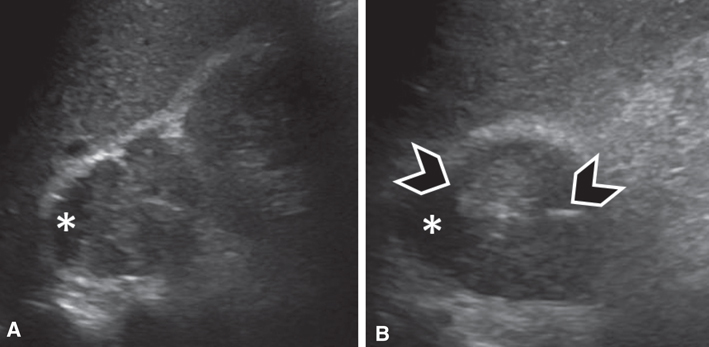

Fig 2

Figure 2 Pheochromocytoma in a 45-year-old male patient. (A) Sagittal and (B) axial ultrasound images of the right adrenal region demonstrate a lesion of heterogeneous echogenicity between the liver (top portion of A and B) and the right kidney (right side of A). The lesion contains a cystic component (asterisk) as well as echogenic foci (arrowheads), suggesting calcifications.